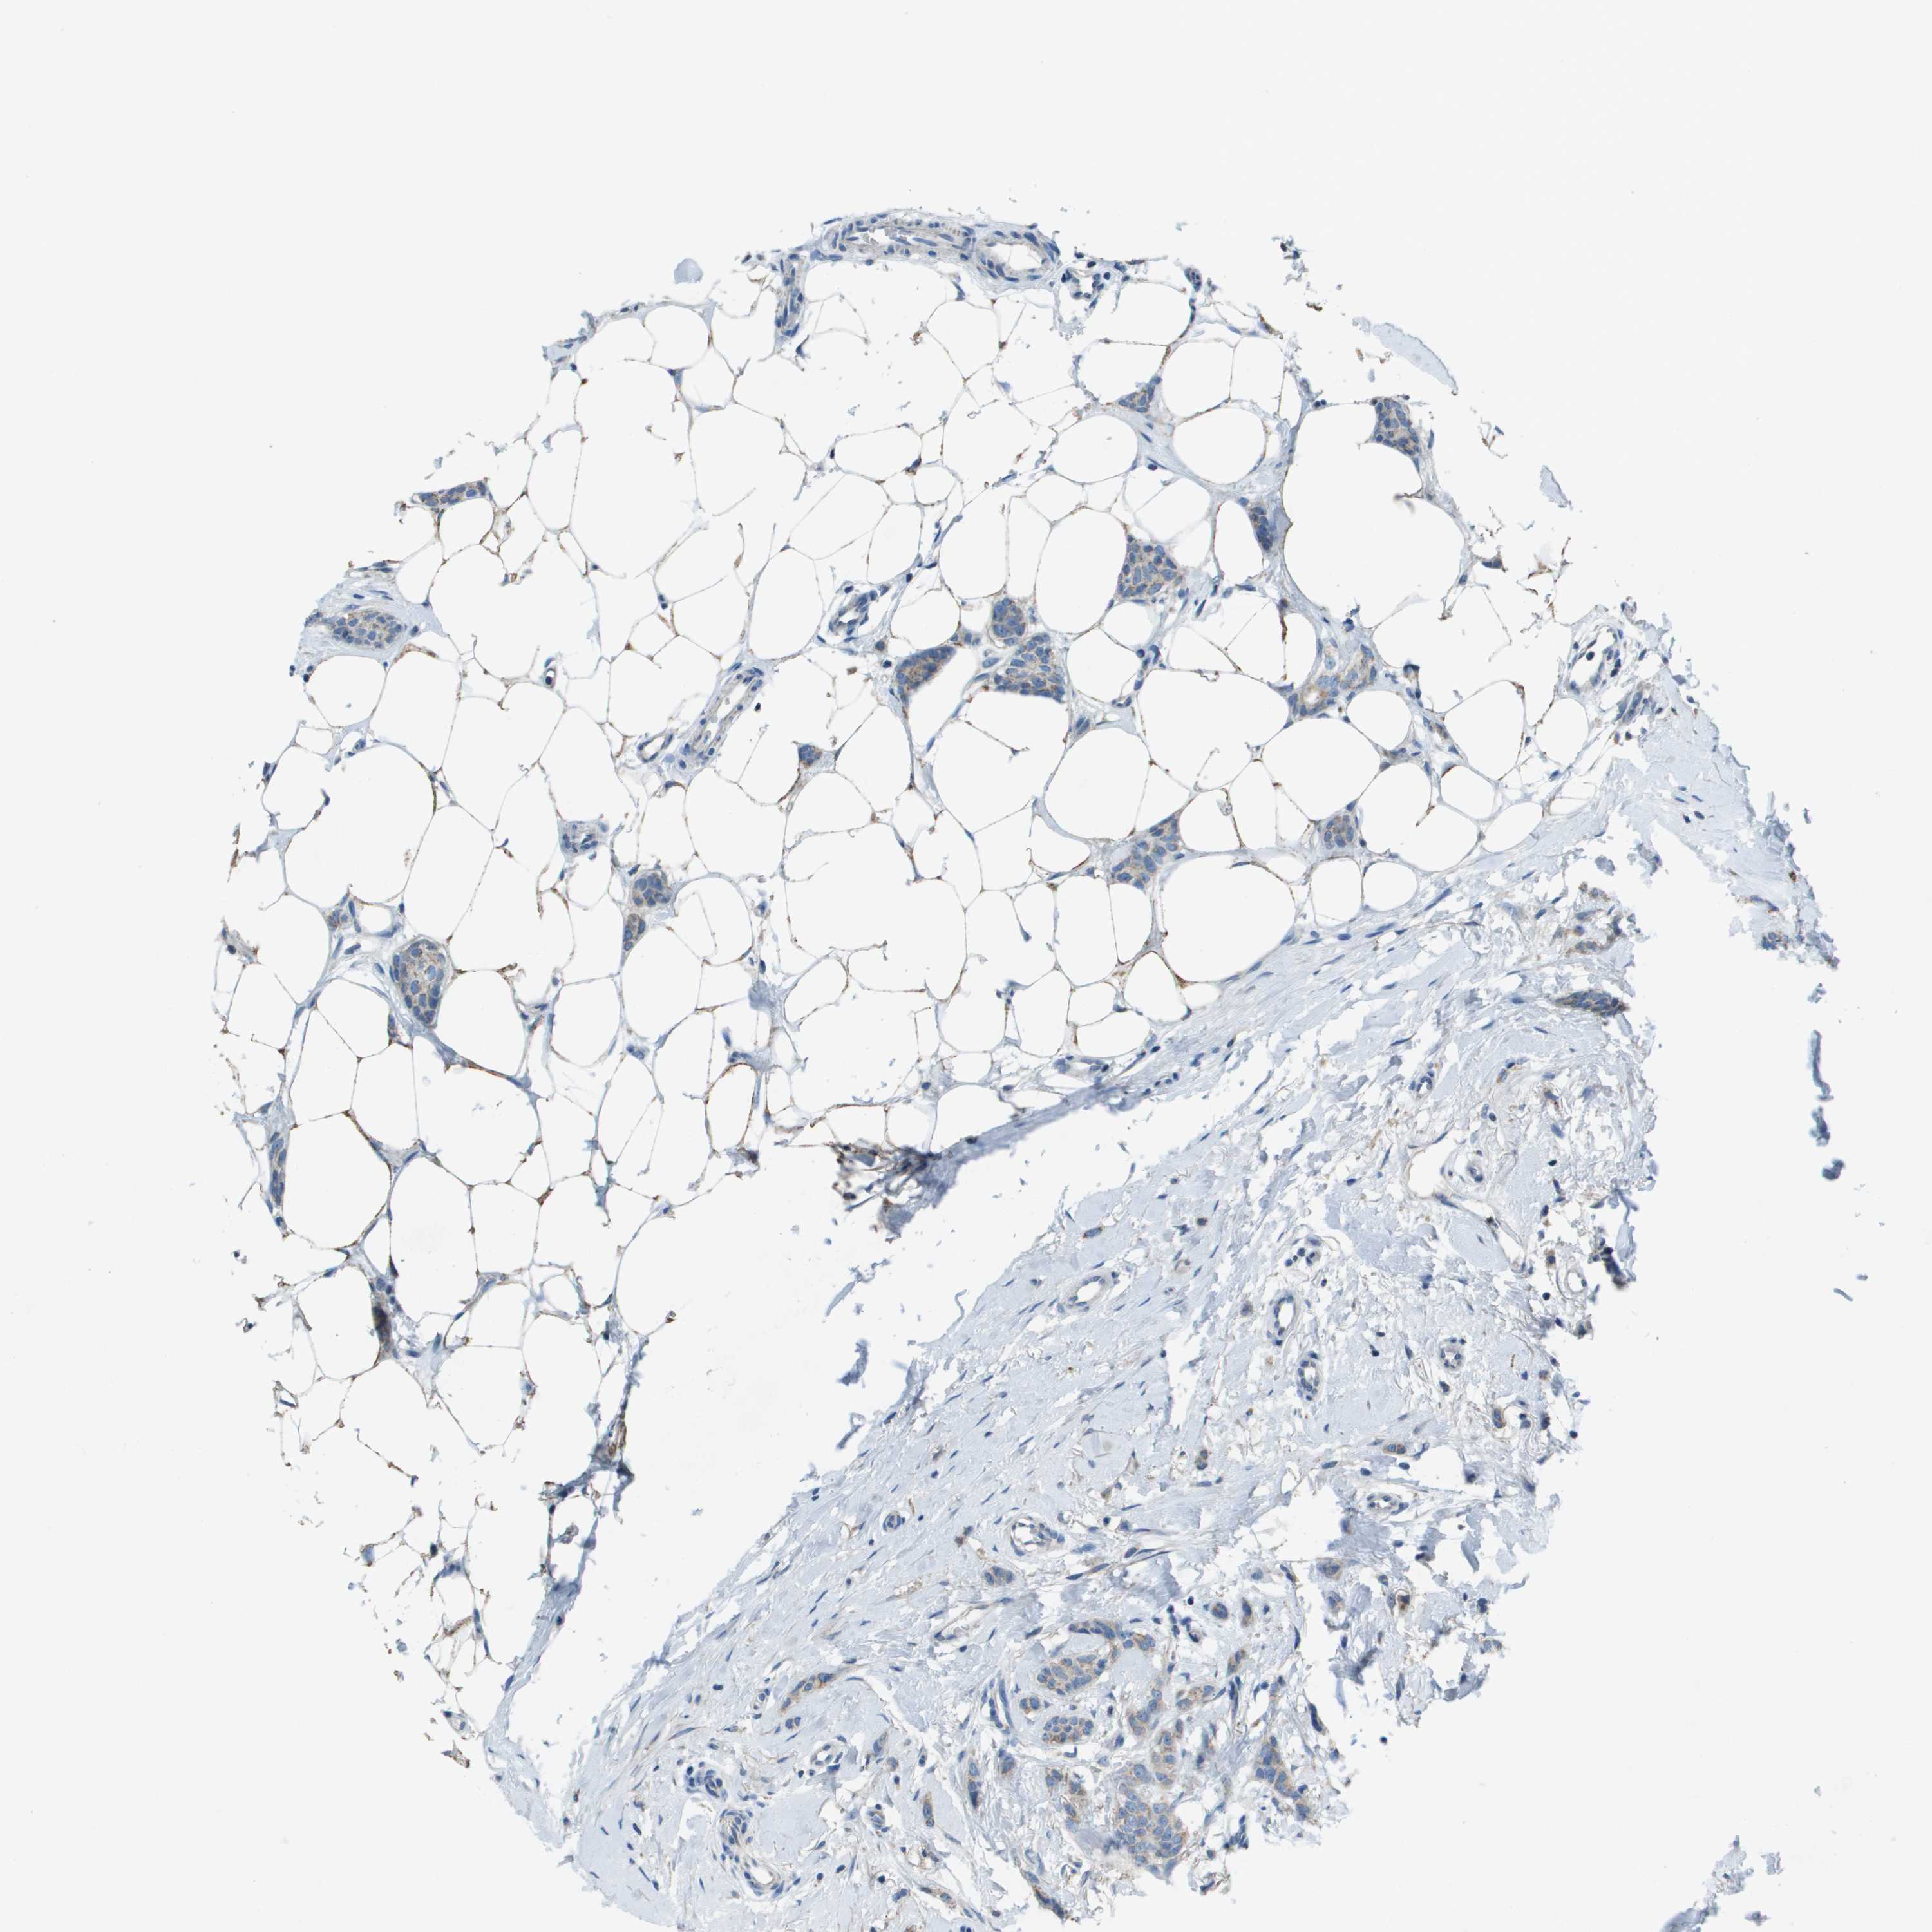

BRCA TCGA BRCA VALIDATION PROTEIN EXPRESSION

ANTIBODIES

AND

VALIDATION